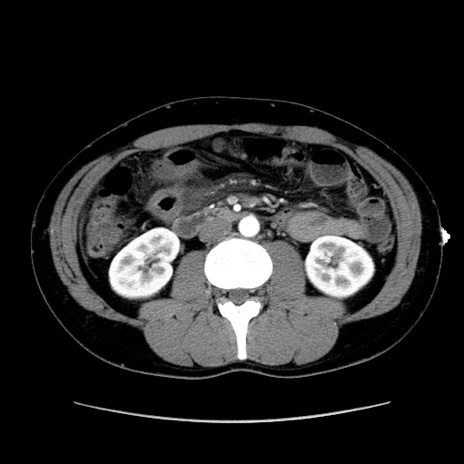

冠状断像

【症例】20歳代 男性

【主訴】心窩部痛

【現病歴】今朝より上腹部痛あり。一旦軽快していたが再度出現したため救急要請。昨日夕に白身の魚を含む刺身を食べた。

【身体所見】BP 136/89mmHg、HR 74/min、BT 37.0℃、腹部:膨満、軟、心窩部に圧痛あり。反跳痛なし、筋性防御なし、腸雑音やや亢進あり。

【データ】WBC 17700、CRP 0.48